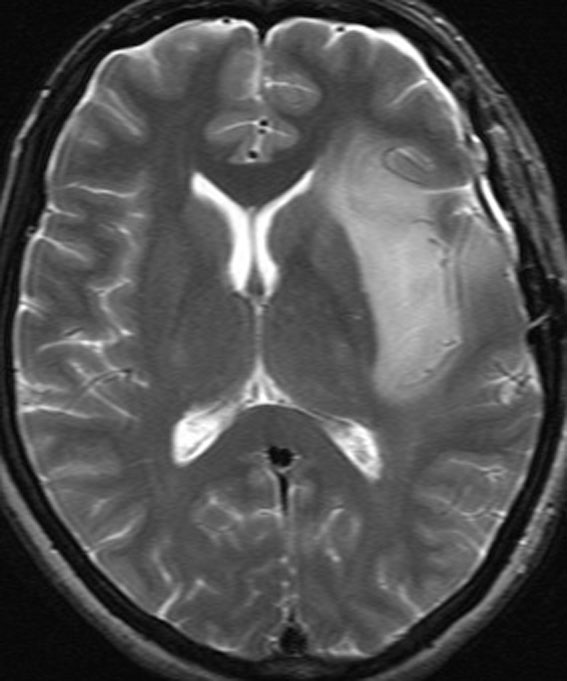

ゆっくり進行する軽い右麻痺で発症した50歳くらいの患者さんです。脳梗塞や脱髄疾患を疑われていました。左頭頂部皮質下から脳梁,内包,中脳大脳脚まで非常に広範囲に浸潤しています。single cell infiltrationという浸潤形態を想像させます。右下はT!ガドリニウム造影で,この部分だけが増強所見があります。

おそらく今後は,diffuse hemispheric glioma WHO grade 4と診断されます。

軽度の異型性を認め,細胞密度が高く核分裂が目立ち,Ki-67 (MIB)染色率は20%に達しました。1p/19q欠失はなくMGMTメチレーションもありませんでした。IDH変異は調べていない年代の例で不明です。病理組織診断でanaplastic astrocytomaとされました。治療は,全脳に近い照射野となるので50Gy/25分割が限界でした。TMZを併用しています。

照射後も症状は一度も改善することなく悪化して,数ヶ月後にはもともと腫瘍が見えなかった内側側頭葉に大きな腫瘍塊が発生増大しました。この例は退形成性星細胞腫と診断するしかなかったものですが,2020年時点でははっきり分類できない星細胞系腫瘍です。